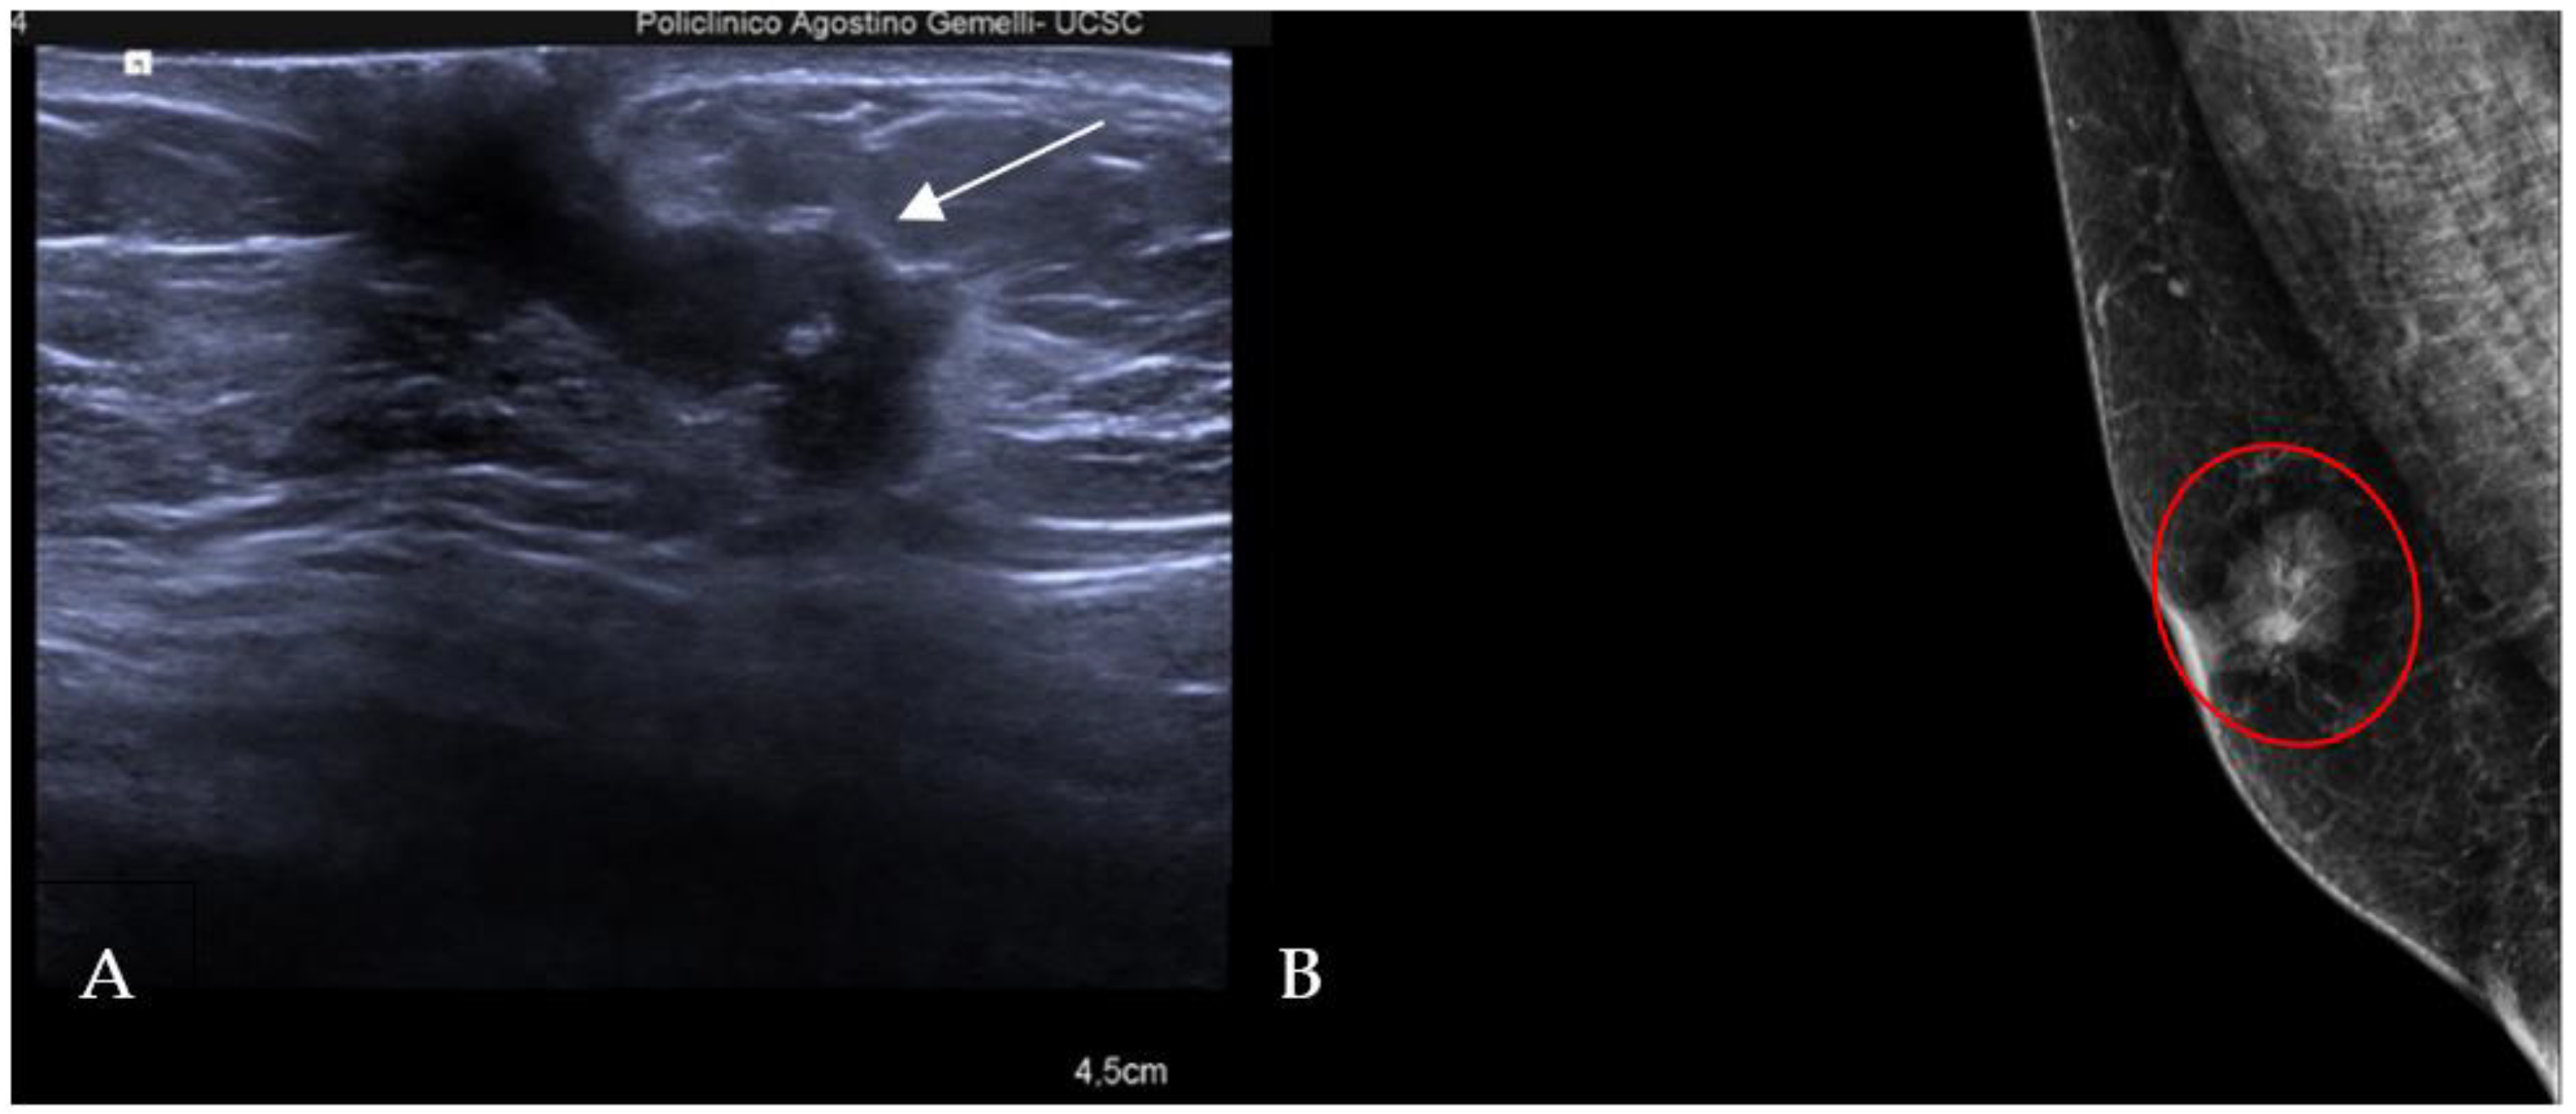

The most common histological subtype of primary malignant breast lesions in men is invasive ductal carcinoma (IDC) [27,28], shown in Figure 7.

Figure 7.

A 60-year-old man with gynecomastia presenting a retroareolar lump on the right breast with nipple retraction and without nipple discharge. Histological examination revealed an invasive ductal carcinoma (ER + 90%, PR + 60%, HER2 score 1+). Ultrasound examination (A) shows a hypoechoic irregular mass (white arrow) in the retroareolar region, with lobulated margins. A mammography (B) shows an irregular hyperdense retroareolar mass with lobulated margins (red circle).

IDC typically originates from the terminal duct–lobular unit [28,29]. Clinical features include a palpable unilateral retroareolar mass with nipple retraction and skin thickening [28,29]. Around 25% of cases may present with bloody nipple discharge [28]. IDC can be associated with ductal in situ components in up to 50% of cases [30]. Mammographically, IDC appears as a retroareolar irregular high-density mass with spiculated or micro-lobulated margins [30,31]. Unlike in women, IDC in men is rarely associated with microcalcifications due to the involution of the ductal system caused by the absence of estrogen and progesterone stimulation [28,29]. Ultrasonography reveals solid, hypoechoic, and irregular masses with margins ranging from microlobulated to spiculated [32]. Papillary carcinoma (PC) is the second most common invasive subtype of MBC and has a higher incidence in men compared to women [33]. PC is characterized by neoplastic proliferation of cells with fibrovascular stalks lacking an intact myoepithelial cell layer [34]. It typically presents with bloody nipple discharge and occurs in the subareolar region. Mammographically, PC may exhibit well-circumscribed or spiculated margins, while ultrasound imaging may reveal a dilated duct or cyst, often appearing as a complex cyst with solid papillary projections along the cyst wall [35,36] (Figure 8).

Figure 8.

Invasive papillary carcinoma in a 59-year-old man with bloody nipple discharge. Magnification of mediolateral oblique view of the right breast (A) shows a focal high-density mass with well-circumscribed margins (red circle). Ultrasound (B) shows a complex cyst with mixed solid and cystic morphologic features.